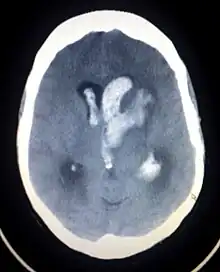

| Axial CT scan of a spontaneous intracranial hemorrhage | |